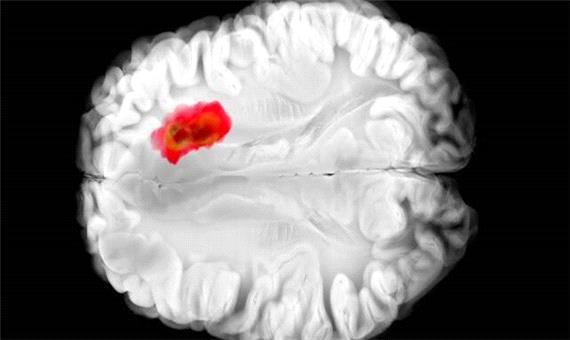

کشف دارویی برای مبارزه با کشنده‌ترین سرطان‌های مغز

سیاست و بازاریابی - ایسنا /به نظر می‌رسد یک دارو که پیش از این برای کنترل فشار خون بالا استفاده می‌شد، با یکی از کشنده‌ترین سرطان‌های مغز مبارزه می‌کند.

تصور می‌شود که همین آنزیم در سرطان‌های مغزی گلیوبلاستومای تهاجمی نقش دارد. این درک جدید از «هیدرالازین» می‌تواند راه را برای درمان‌های جدید سرطان هموار کند و همچنین اثربخشی دارو را برای اهداف فعلی آن بهبود بخشد.

مطالعات قبلی نشان داده‌اند که تومورهای گلیوبلاستوما اغلب سرشار از ADO هستند و آن را برای تولید ماده شیمیایی به نام هیپوتائورین(hypotaurine) می‌ربایند که به سلول‌های سرطانی کمک می‌کند تا گسترش یابند، برای مدت طولانی‌تری زنده بمانند و فشار را تحمل کنند.

در آزمایش‌هایی که با سلول‌های گلیوبلاستومای انسانی انجام شد، «هیدرالازین» با مسدود کردن ADO رشد تومور را متوقف کرد.